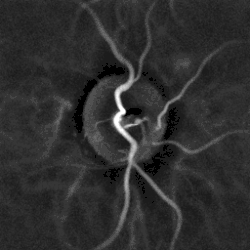

Laser Doppler imaging of the papilla of a patient with hypertension

• Strongly modulated blood flow pulse in central and branch arteries can result from hypertension. Microangiography by laser Doppler imaging[3] may reveal altered hemodynamics non-invasively.